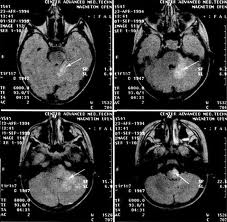

Доброкачественная лимфоцитома, или лимфаденоз кожи (lymphadenosk benigna ciihs), представляет собой опухолеподобное уплотнение, обычно на мочке уха, в области соска молочной железы или мошонки (наиболее частые локализации) и иногда на других участках кожи. В этот период могут возникать неврологические симптомы, включающие поражение как центральной (менингит, энцефалит. миелит, энцефалопатия), так и периферической (краниальные невропатии, радикулопатии, периферическая нейропатия, множественные мононевриты, плечевая плексопатия, пояснично-крестцовая плексопатия, Гийена Барре-подобный синдром, моторная нейропатия и др.) нервной системы. Для поражения сердца характерны нарушения ритма и проводимости (атриовентрикулярные блокады), редко обнаруживают субклинически протекающий мио- и/или перикардит.

Поздняя стадия заболевания. Для поздней стадии болезни Лайма характерно поражение кожи по типу хронического атрофического акродерматита относительно редкого заболевания с вовлечением разгибательных поверхностей дистальных отделов конечностей. Начало процесса - инфильтративно-воспалительная фаза, за которой через годы следует атрофическая фаза. Иногда происходит присоединение склеротического процесса, очень напоминающего склеродермию. Среди других проявлений поздней стадии полинейропатия, прогрессирующий энцефаломиелит.